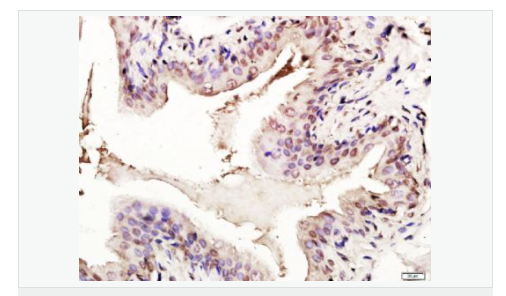

| 產(chǎn)品應(yīng)用 | WB=1:1000-2000 ELISA=1:1000-5000 IHC-P=1:100-500 IHC-F=1:100-500 Flow-Cyt=1ug/Test ICC=1:100-500 IF=1:100-500 (石蠟切片需做抗原修復) not yet tested in other applications. optimal dilutions/concentrations should be determined by the end user. |

| 細胞定位 | 細胞核 細胞漿 |